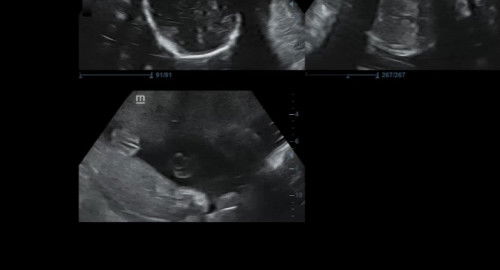

Cewe/Cowo?

Bun kalo ini 100persen cewe kah?#sharing #firstmom #bantujawab